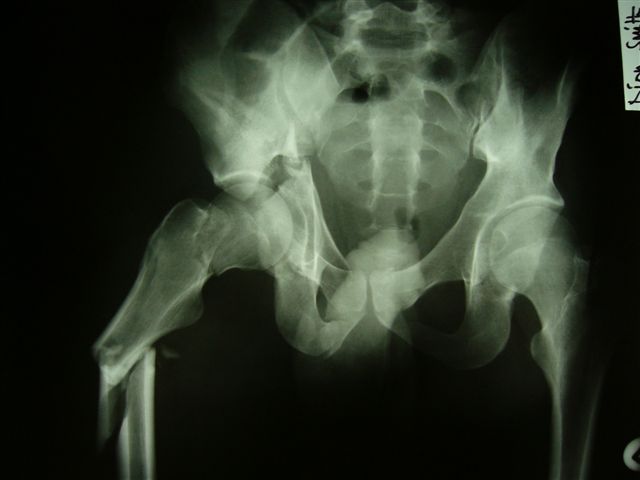

Anatoly F Lazarev 03 Сентябрь 2004, 22:18

Женя! Класный перелом. Отлично репонируется изнутри таза, но лучше фиксированть сзади. Классический перелом для двустороннего доступа.

Однако есть альтернатива. Репозиция из подвздошного доступа тазовыми щипцами с разнодлинными браншами или тазовым пистолетом, а фиксация задней колонны через седалищный бугор или тазрвыми винтами 4,5 или каннюлированными 6,5 или 7,3. По-моему я посылал на ортофорум такой снимок, когда жаловался на ишемический неврит седалищного нерва через сутки после операции. Не забудь про шейку бедра - мне кажется будет хорош длинный PFN любой фирмы, какую ты найдешь, а нет так UFN + miss a nail, как это здорово делают мои земляки - Ебурбуки. Пока.

Высылаю пример еще одного случая, остеосинтез пластиной из подвздошного доступа.